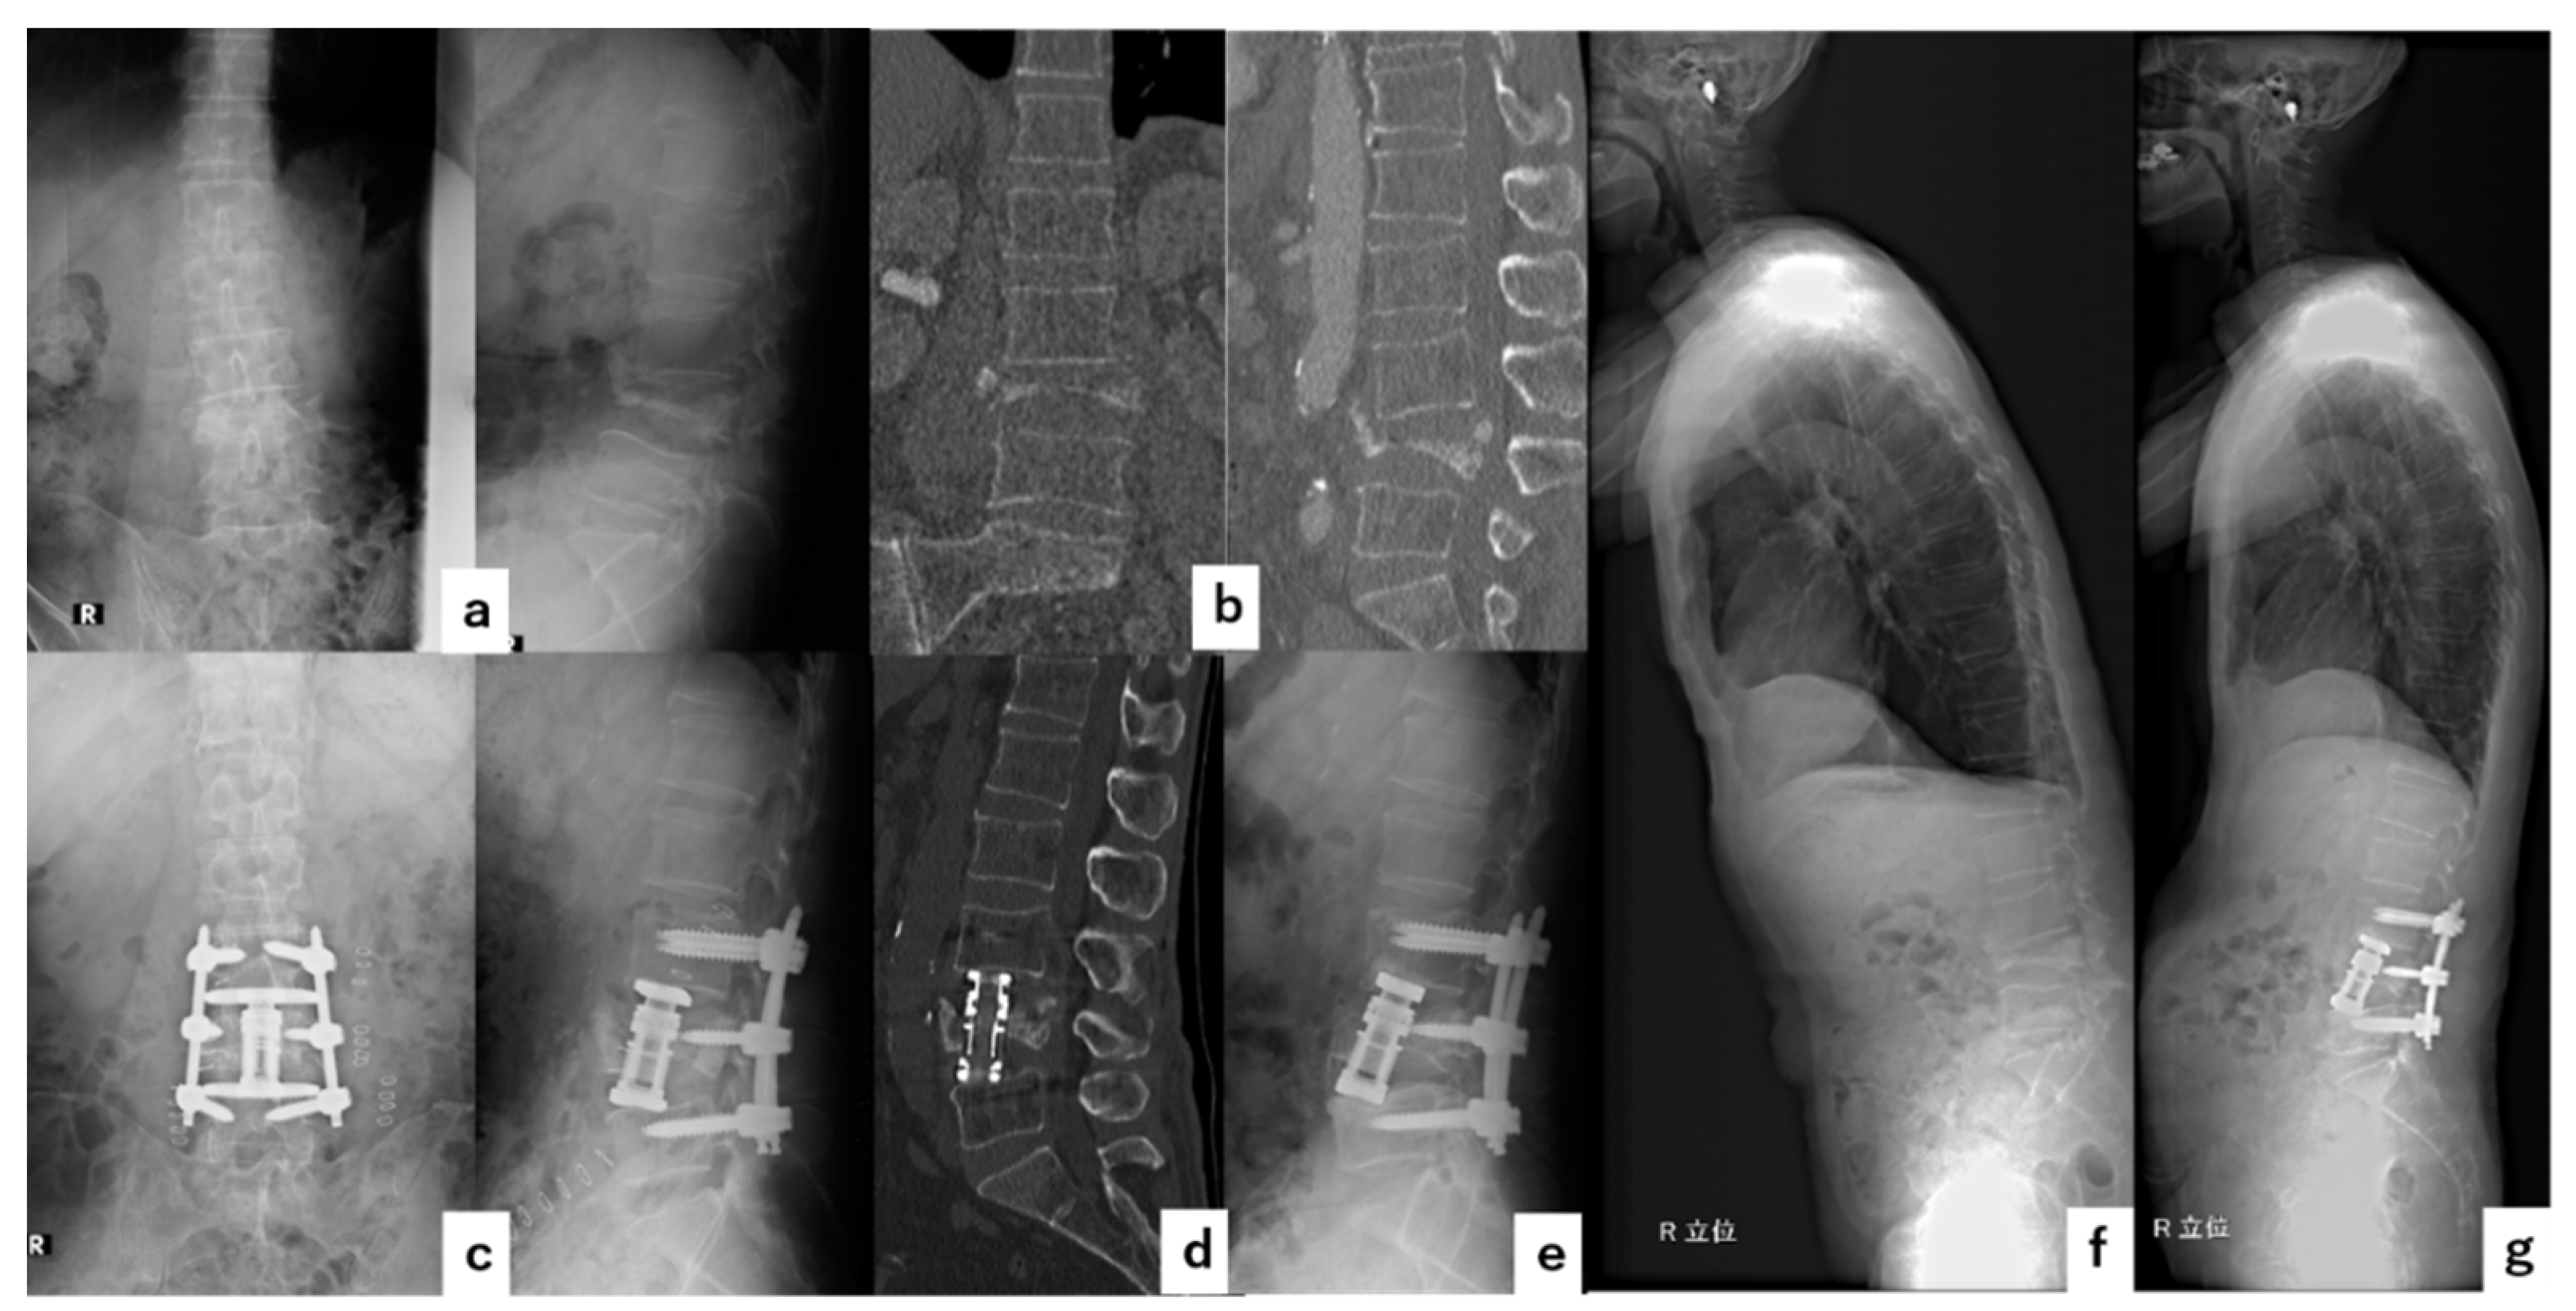

4. Illustrative Cases

4.1. Case 1

4.2. Case 2